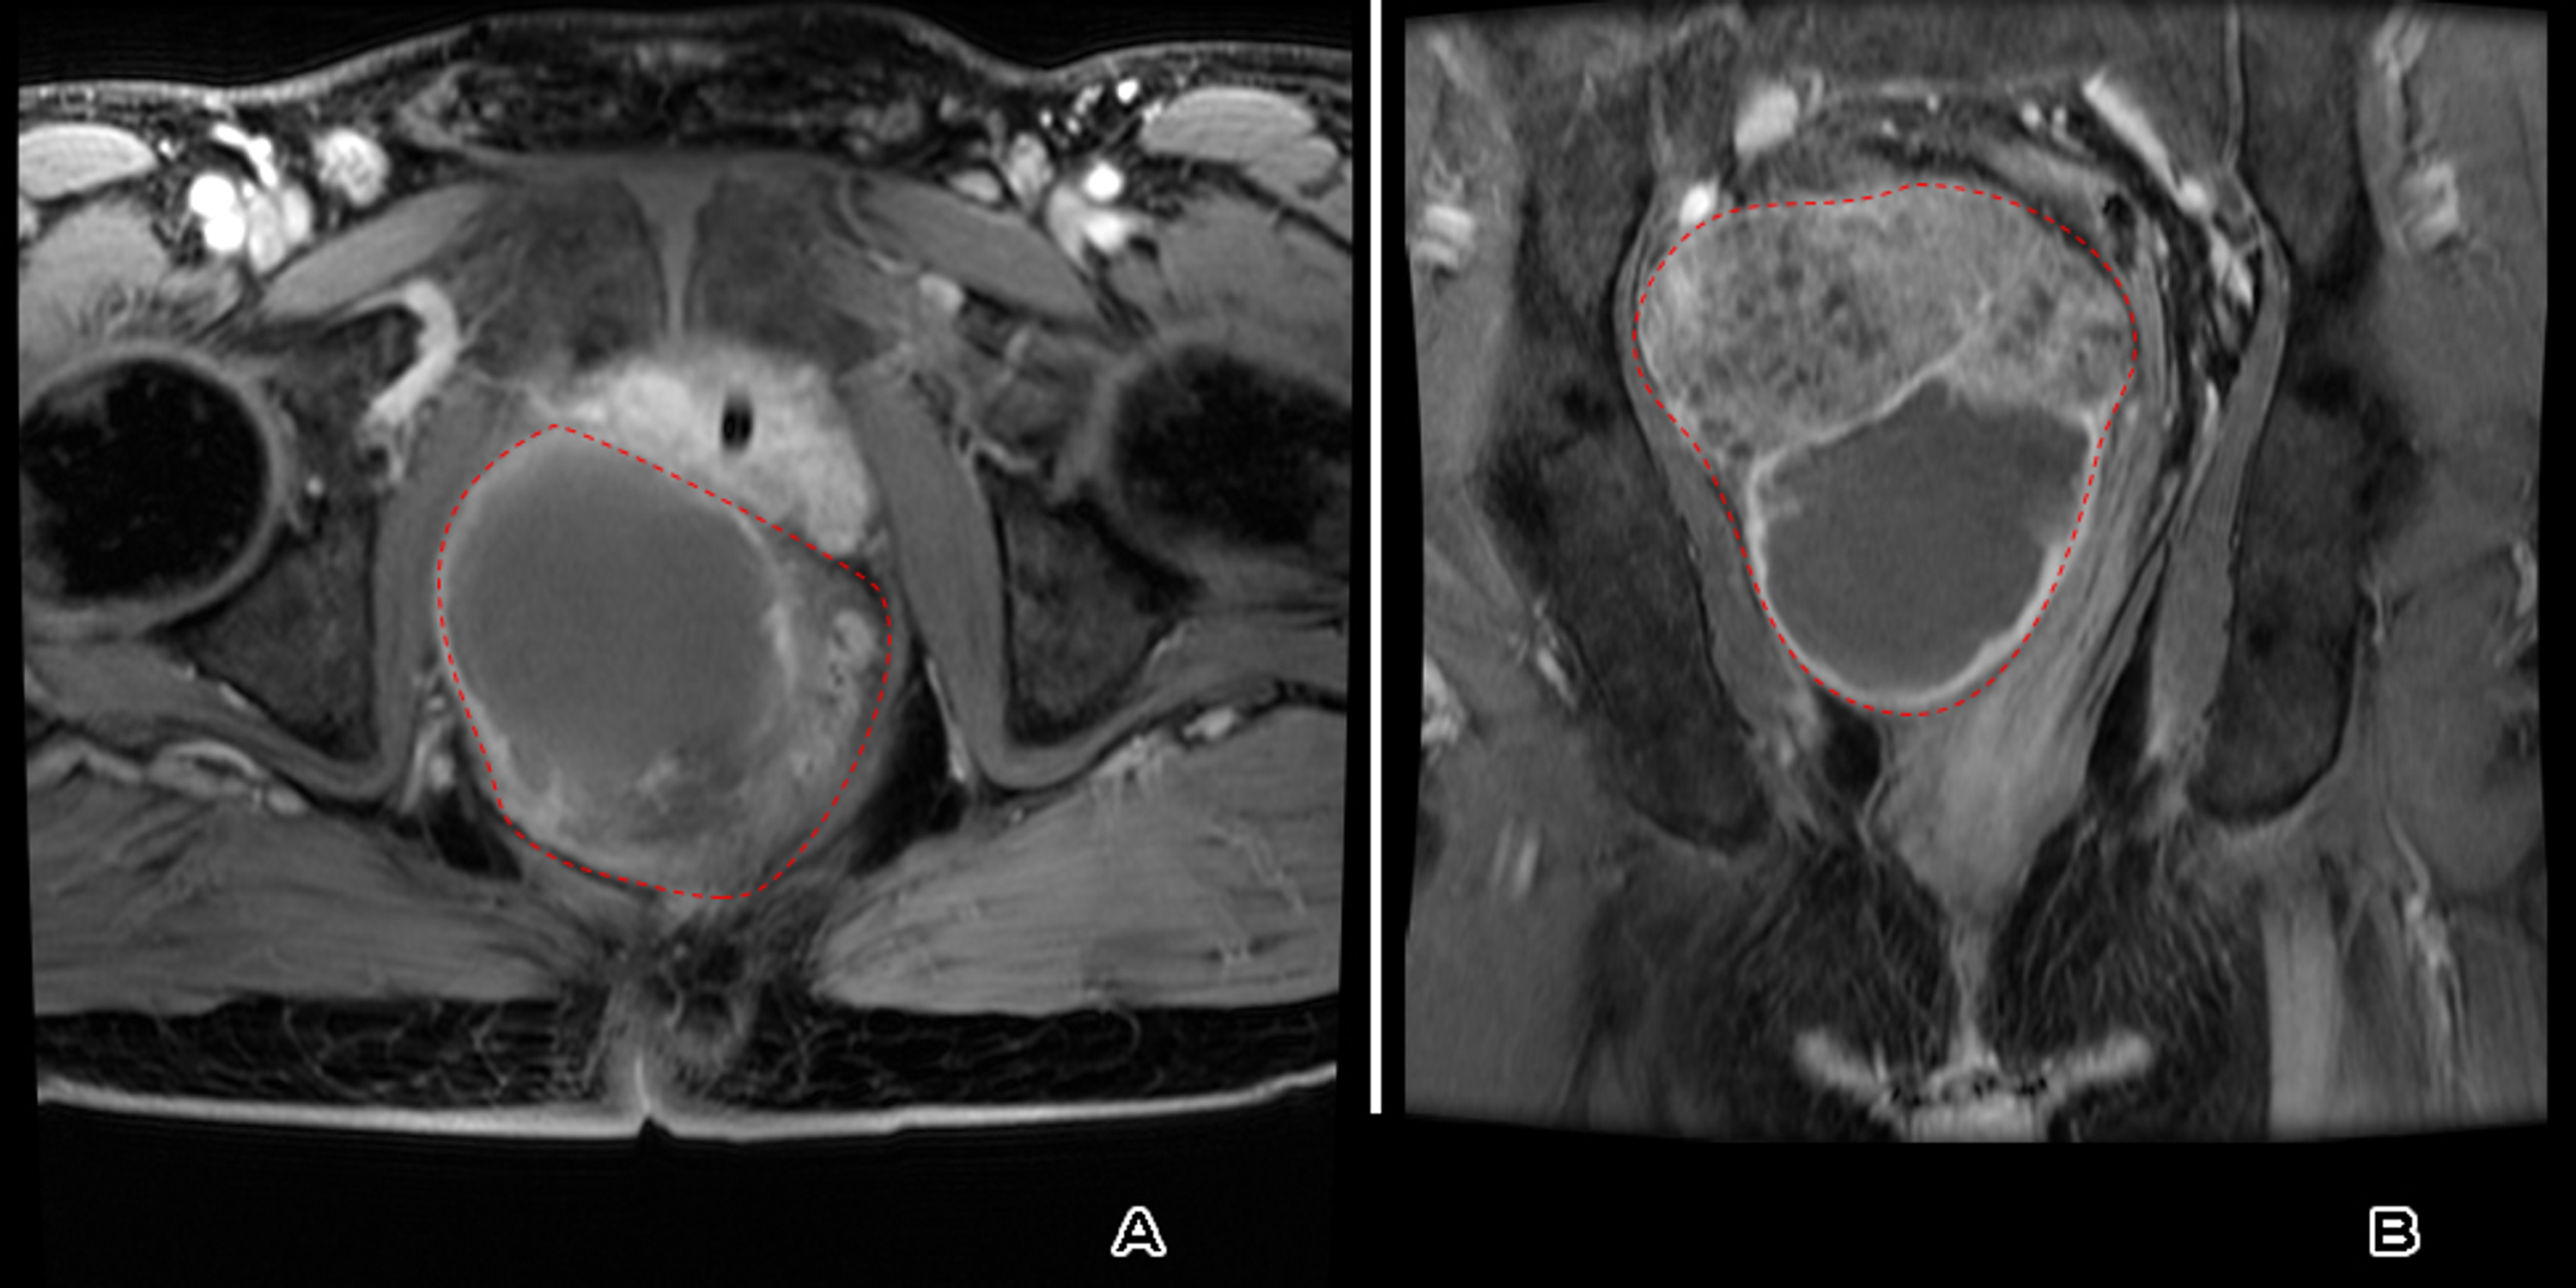

Pelvic Bone Sarcomas Controversies And Treatment Options In Journal Of The National Comprehensive Cancer Network Volume 8 Issue 6 2010

Results Of Surgical Resection In Pelvic Ewing S Sarcoma Puri 2012 Journal Of Surgical Oncology Wiley Online Library

Treatment Outcomes After Proton Therapy For Ewing Sarcoma Of The Pelvis International Journal Of Radiation Oncology Biology Physics